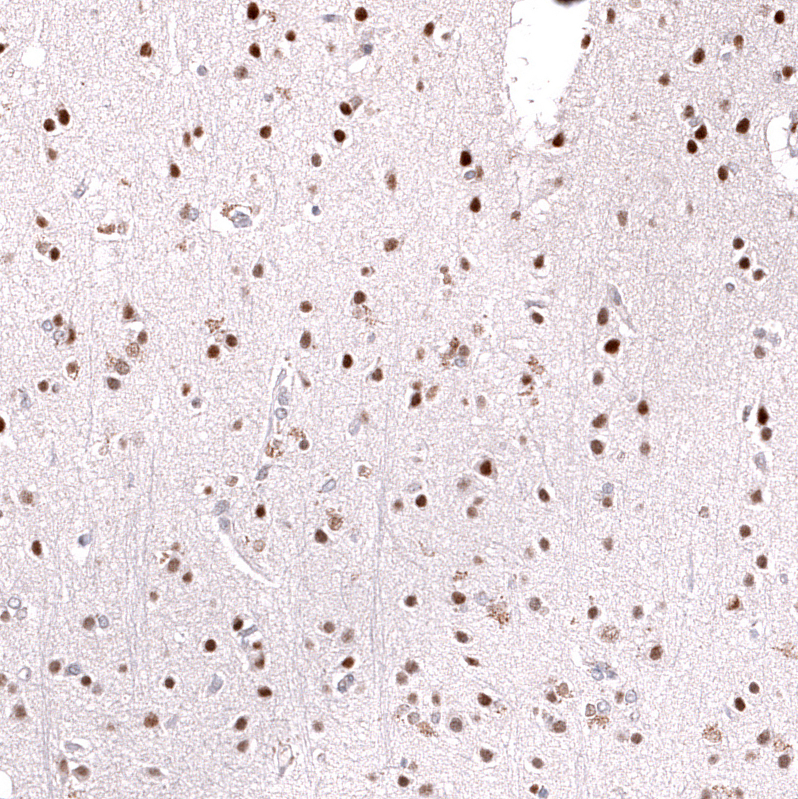

Immunohistochemical staining of human anaplastic oligodendroglioma shows strong nuclear positivity in tumor cells.